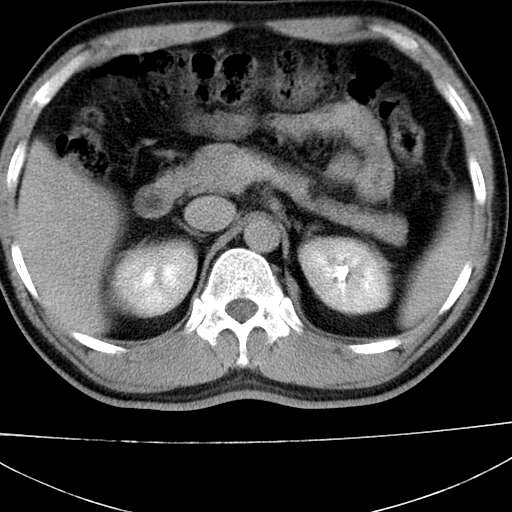

标题: CT21921:腹膜后腔肿物。患者男39Y。体检。增强扫描时间欠准 [打印本页]

标题: CT21921:腹膜后腔肿物。患者男39Y。体检。增强扫描时间欠准

1)考虑左肺下叶后基底段(或左下胸后壁胸膜)软组织团块,性质待定;建议行进一步检查。2)左肾结石。

左膈肌角后腹膜腔见肿物影,其内见脂肪密度灶及软组织密度灶,强化不明显。病灶大部在后腹膜内。考虑异位嗜铬细胞瘤或脂肪肉瘤、畸胎瘤

1)考虑左肺下叶后基底段软组织团块,性质待定;建议行进一步检查。2)左肾结石。

左膈肌连续性中断,左侧膈疝可能性大

左下肺隔离症,可见从胸主动脉发出异常血管供应